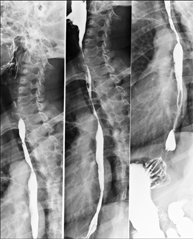

- Spinal teleradiology

This technique uses X-ray rendered imaging to examine the entire spinal column, especially assessing the presence of scoliosis and pelvic dysmetria.

Tècnica que usa els raigs X a través de la qual s'obtenen imatges de la columna dorsal per al seu estudi. Indicacions: traumatisme, dolor, escoliosi. - Esofagograma

Tècnica que usa els raigs X a través de la qual s'obtenen imatges de l'abdomen (estómac, intestí prim, intestí gros, fetge, ronyons, bufeta, pelvis òssia, etc.) per al seu estudi. - RX Columna lumbar

Tècnica que usa els raigs X a través de la qual s'obtenen imatges de la columna lumbar per al seu estudi. - TEGD (trànsit esòfag-gastro-duodenal)